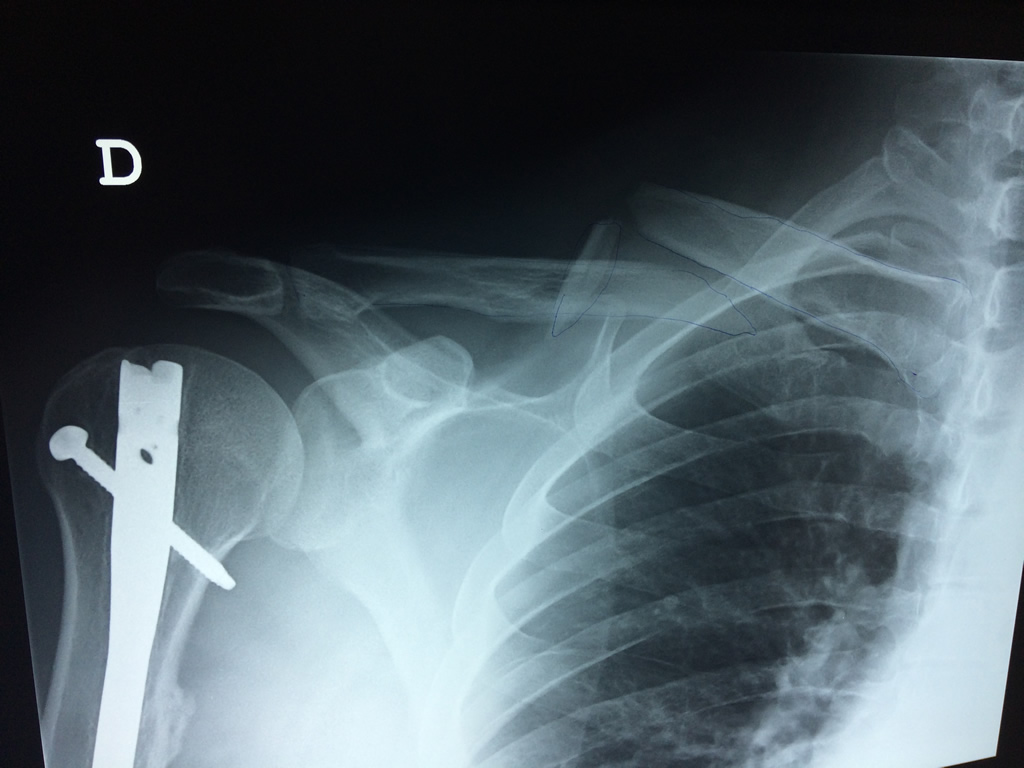

Cirugías